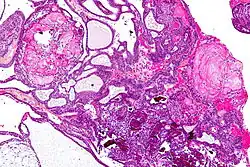

Патологическая анатомия

В зависимости от структуры различают два основных вида краниофарингиом — состоящий из плотной ткани и кистозный. В диаметре их размер колеблется от 2 до 5 см, реже больше. Растёт медленно, экспансивно. Кистозно перерождённые участки опухоли содержат от 10 до 50 (в редких случаях до 200) мл жидкости жёлтого, янтарного или кофейного цвета. Имеет плотную капсулу, довольно прочно связанную с окружающей её мозговой тканью, оболочками и сосудистой сетью. Кровоснабжение опухоли осуществляется из ветвей артериального круга большого мозга[1].

Структура краниофарингиомы с течением времени может значительно видоизменяться. В её компактных слоях происходит колликвационный некроз с формированием кист, которые содержат жидкость с большим содержанием белка (от 20 до 100 ‰ и более), кристаллов холестерина и жирных кислот. На внутренней поверхности капсулы происходит отложение солей. Гистологически краниофарингиомы состоят из эпителиальных клеток различной степени дифференциации. Выделяют адамантиматозный и папиллярный гистологические варианты строения краниофарингиомы[29]. Наряду с эпителиальными клетками эмбрионального типа встречается и эпителий эпидермального типа. Клеточные скопления в ряде случаев могут напоминать адамантиномы. Также в краниофарингиомах всегда наблюдаются дистрофические изменения различной степени выраженности в виде кистообразования, обызвествления или даже оссификации стромы. Капсула состоит из соединительной или глиальной тканей. Разнообразие в строении краниофарингиом может расцениваться как результат фазности развития новообразования[1].